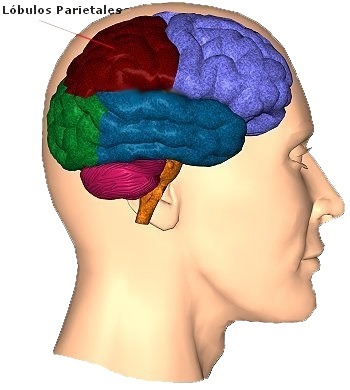

Ubicación

El área de Broca ubicada en la tercera circunvolución frontal (en el lóbulo frontal) del hemisferio cerebral izquierdo, si bien en algunos casos excepcionales se encuentra en el hemisferio derecho. Concretamente, según el mapa de Brodmann, ocupa las áreas 44 y 45 de Brodmann, cerca del ojo y pegado a la parte frontal del lóbulo temporal.